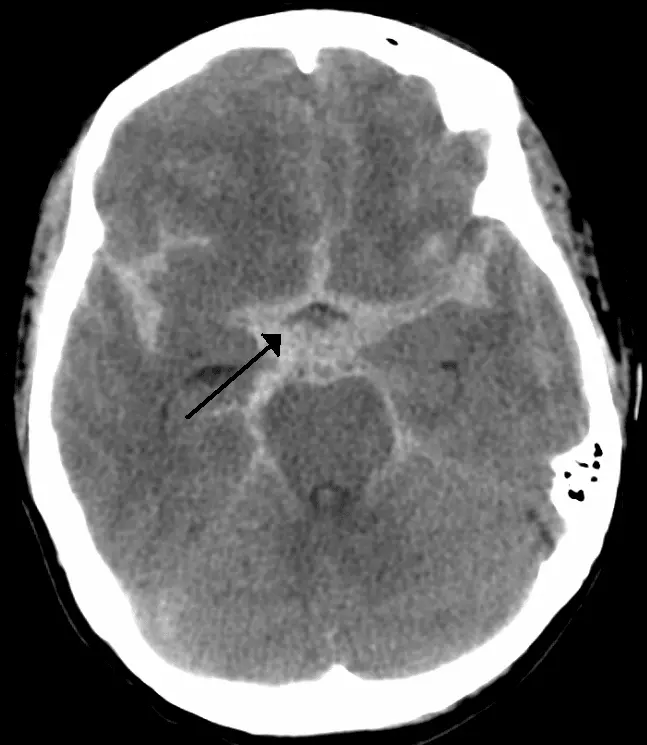

- Subarachnoid - bleeding from one of the cerebral arteries. Can be spontaneous (ruptured berry aneurysm) or traumatic. The classical CT appearance is a central star-shaped area of hyperdensity as blood enters the subarachnoid space and collects within the basal cisterns.

Image - Axial CT head showing a spontaneous subarachnoid haemorrhage

Creative commons source by James Heilman, MD [CC BY-SA 4.0 (https://creativecommons.org/licenses/by-sa/4.0)]